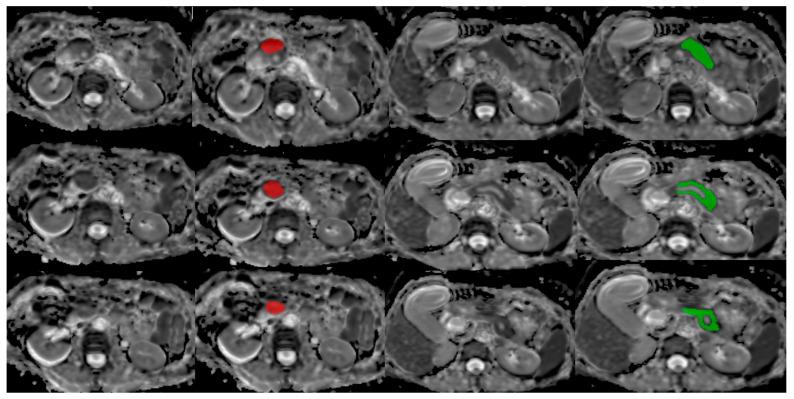

We observed T2W-FS and ADC images obtained by 1.5T-MR of 87 patients with histologically proven pancreatic adenocarcinoma for training and validation purposes and then tested the most accurate predictive models that were obtained on another group of 58 patients. The tumor and surrounding pancreatic tissue were segmented on three consecutive slices, with the largest area of interest (ROI) of tumor marked using MaZda v4.6 software. This resulted in a total of 261 ROIs for each of the observed tissue classes in the training-validation group and 174 ROIs in the testing group. The software extracted a total of 304 radiomic features for each ROI, divided into six categories. The analysis was conducted through six different classifier models with six different feature reduction methods and five-fold subject-wise cross-validation.

方法

为了进行训练和验证,我们观察了87例经组织学证实为胰腺腺癌患者的1.5T-MR获取的T2W-FS和ADC图像,然后在另一组58例患者中测试了获得的最准确预测模型。在连续三个切片上对肿瘤和周围胰腺组织进行分割,使用MaZda v4.6软件标记肿瘤的最大感兴趣区域(ROI)。这导致训练-验证组中每个观察到的组织类别共有261个ROI,测试组中有174个ROI。该软件为每个ROI总共提取了304个放射组学特征,分为六类。通过六种不同的分类器模型、六种不同的特征约简方法和五重受试者交叉验证进行分析。